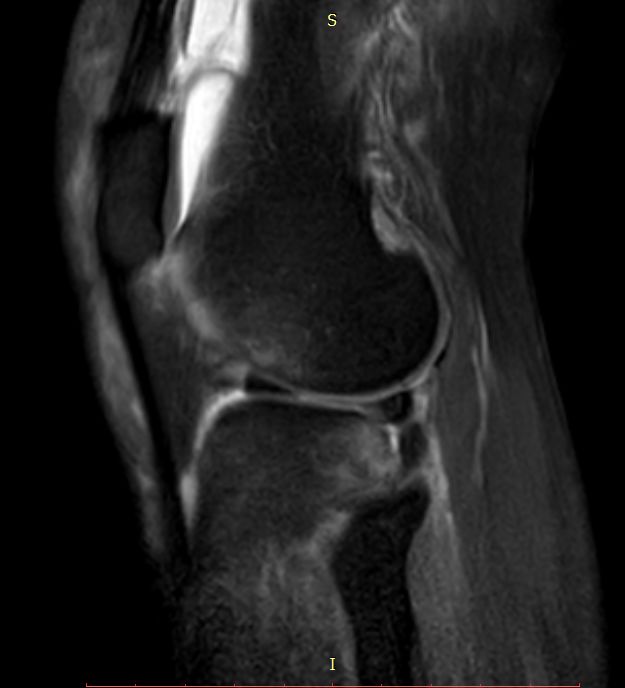

女44岁,外伤

前交叉韧带“消失”

外侧半月板后角“消失”

Segond骨折,因下肢过度内翻、内翻暴力所致胫骨平台外侧缘的撕脱性骨折。撕脱的骨折块较小,小骨片多位于腓骨头上方,且较少波及关节面而易被忽视。往往合并前交叉韧带损伤、半月板损伤及外侧副韧带损伤。

有文献报道,Segond 骨折合并有前交叉韧带(ACL)损伤的发生概率约为75%~100%,若没有得到及时处理,关节将会出现反复扭伤的现象,容易引发膝关节继发性损害,最终将导致关节过早的出现退变和骨关节病的发生。当怀疑Segond骨折,应该做MRI检查,评价膝关节组织损伤情况。